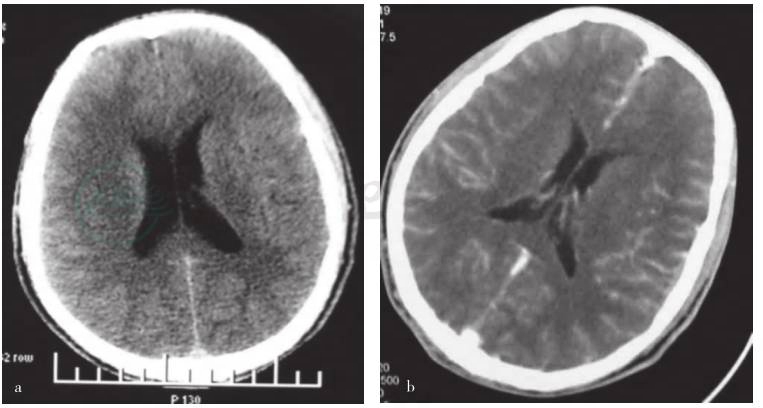

入院后给予对症支持治疗。辅助检查:血气分析,pH 7.405,氧分压(PO2)69.7mmHg,血氧饱和度(SO2)93.3%,PCO2 38.3mmHg,HCO3 23.5mmol/L;血常规,白细胞16.54×109/L,中性粒细胞比例87.1%。心电图正常。头部CT:大脑皮层可疑弥漫性密度增高,双侧脑室轻度增大;头部CT增强:增强可见脑膜异常强化(图2a、b)。肺CT:双肺间质化,以双下肺为著。腹部B超:胆囊内中强回声,息肉?结石?余未见明显异常。毒物筛查:患者血检有低于中毒剂量的地西泮及苯巴比妥,未及百草枯及其他除草剂。当日腰穿:压力85mmHg,细胞总数160×106/L,白细胞数2×106/L,生化:蛋白0.66g/L,葡萄糖3.2mmol/L,氯化物119mmol/L。脑脊液细胞学:散在异型细胞,胞质内可见色素颗粒,建议复查细胞学及免疫组化。次日复查腰穿:压力50mmH2O,细胞总数970×106/L,白细胞数4×106/L,蛋白 0.46g/L,糖与氯化物正常。脑脊液细胞学(自然沉淀法,侯氏脑脊液细胞沉淀器):可见含有黑色素颗粒的异形细胞,免疫染色S-100和HMB45阳性,符合黑色素细胞增生性疾病(图3)。予补液、支持,患者意识无进一步恢复,建议行皮肤活检,家属拒绝,放弃治疗,离院回当地,2天后患者逐渐醒转,逐渐恢复进食及活动,但反应较前迟钝。20天后复查头部MRI增强(图2c、d)显示软脑膜明显异常强化,右顶颞部脑膜下可见异常强化结节;第四脑室及幕上脑室略见扩张;脑实质、脑干及小脑半球未见异常强化信号。8个月后电话随诊,患者仍存活,有幻觉、精神症状,失眠,视力下降较明显,家属诉较病前下降80%左右。间断癫痫大发作,予卡马西平治疗,癫痫大发作明显减少。走路不稳,手足有时抖,但生活大致自理。间断有头痛症状,输甘露醇可部分缓解。皮肤黑痣未见进一步增大或性状改变。拟病情稳定行皮肤活检,但患者精神及智能状况进行性加重,家属未再带患者外出就诊。14个月后电话随诊,患者视力基本丧失,卧床,言语难以理解,认知功能明显下降,定向力、自知力均差,间断有左侧上肢抽动,类似部分性癫痫发作,无自理能力。

a.头部CT平扫显示大脑皮层可疑弥漫性密度增高,双侧脑室轻度增大;b.头部CT增强可见脑膜异常强化;

c.箭头所示为右颞叶异常强化结节影(MRI增强);d.箭头所示为右顶叶异常强化结节影(MRI增强)

图2 患者神经影像学检查